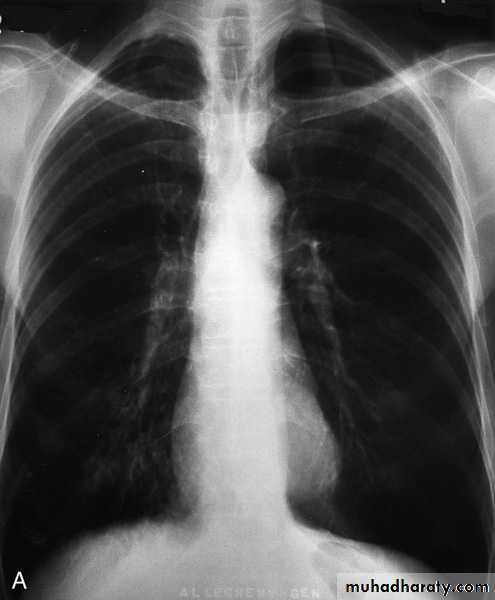

Investigations Imaging

Chest X-ray: Typical changes of emphysema include paucity of parenchymal markings, hyper-translucency and bulae. Increasing lung volume and flattening of diaphragm suggest hyperinflation.